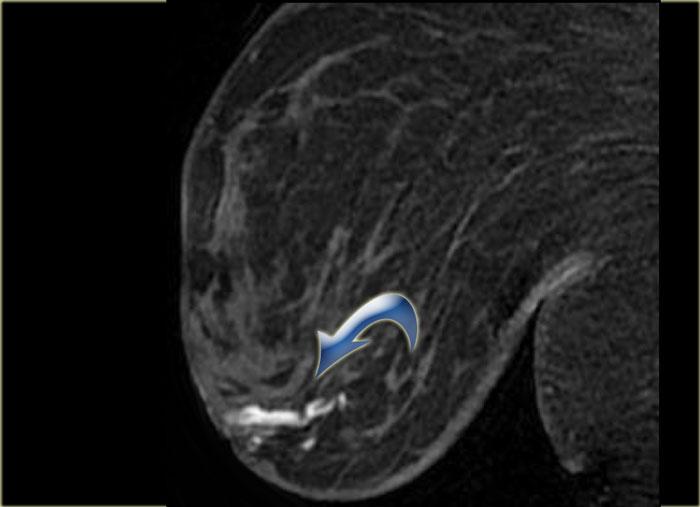

Hình ảnh ngoài cùng bên trái cho thấy một khối bất thường có lan rộng theo ống tuyến, và

bên phải là một khối bất thường lan đến thành ngực nhưng không xâm lấn vào thành ngực.

Không có ngấm thuốc ở thành ngực.